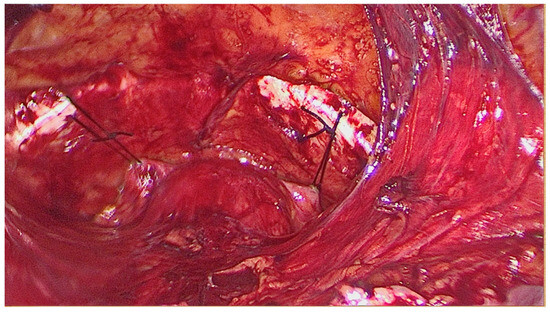

Figure 2.

The anatomical landmarks of Retzius space.